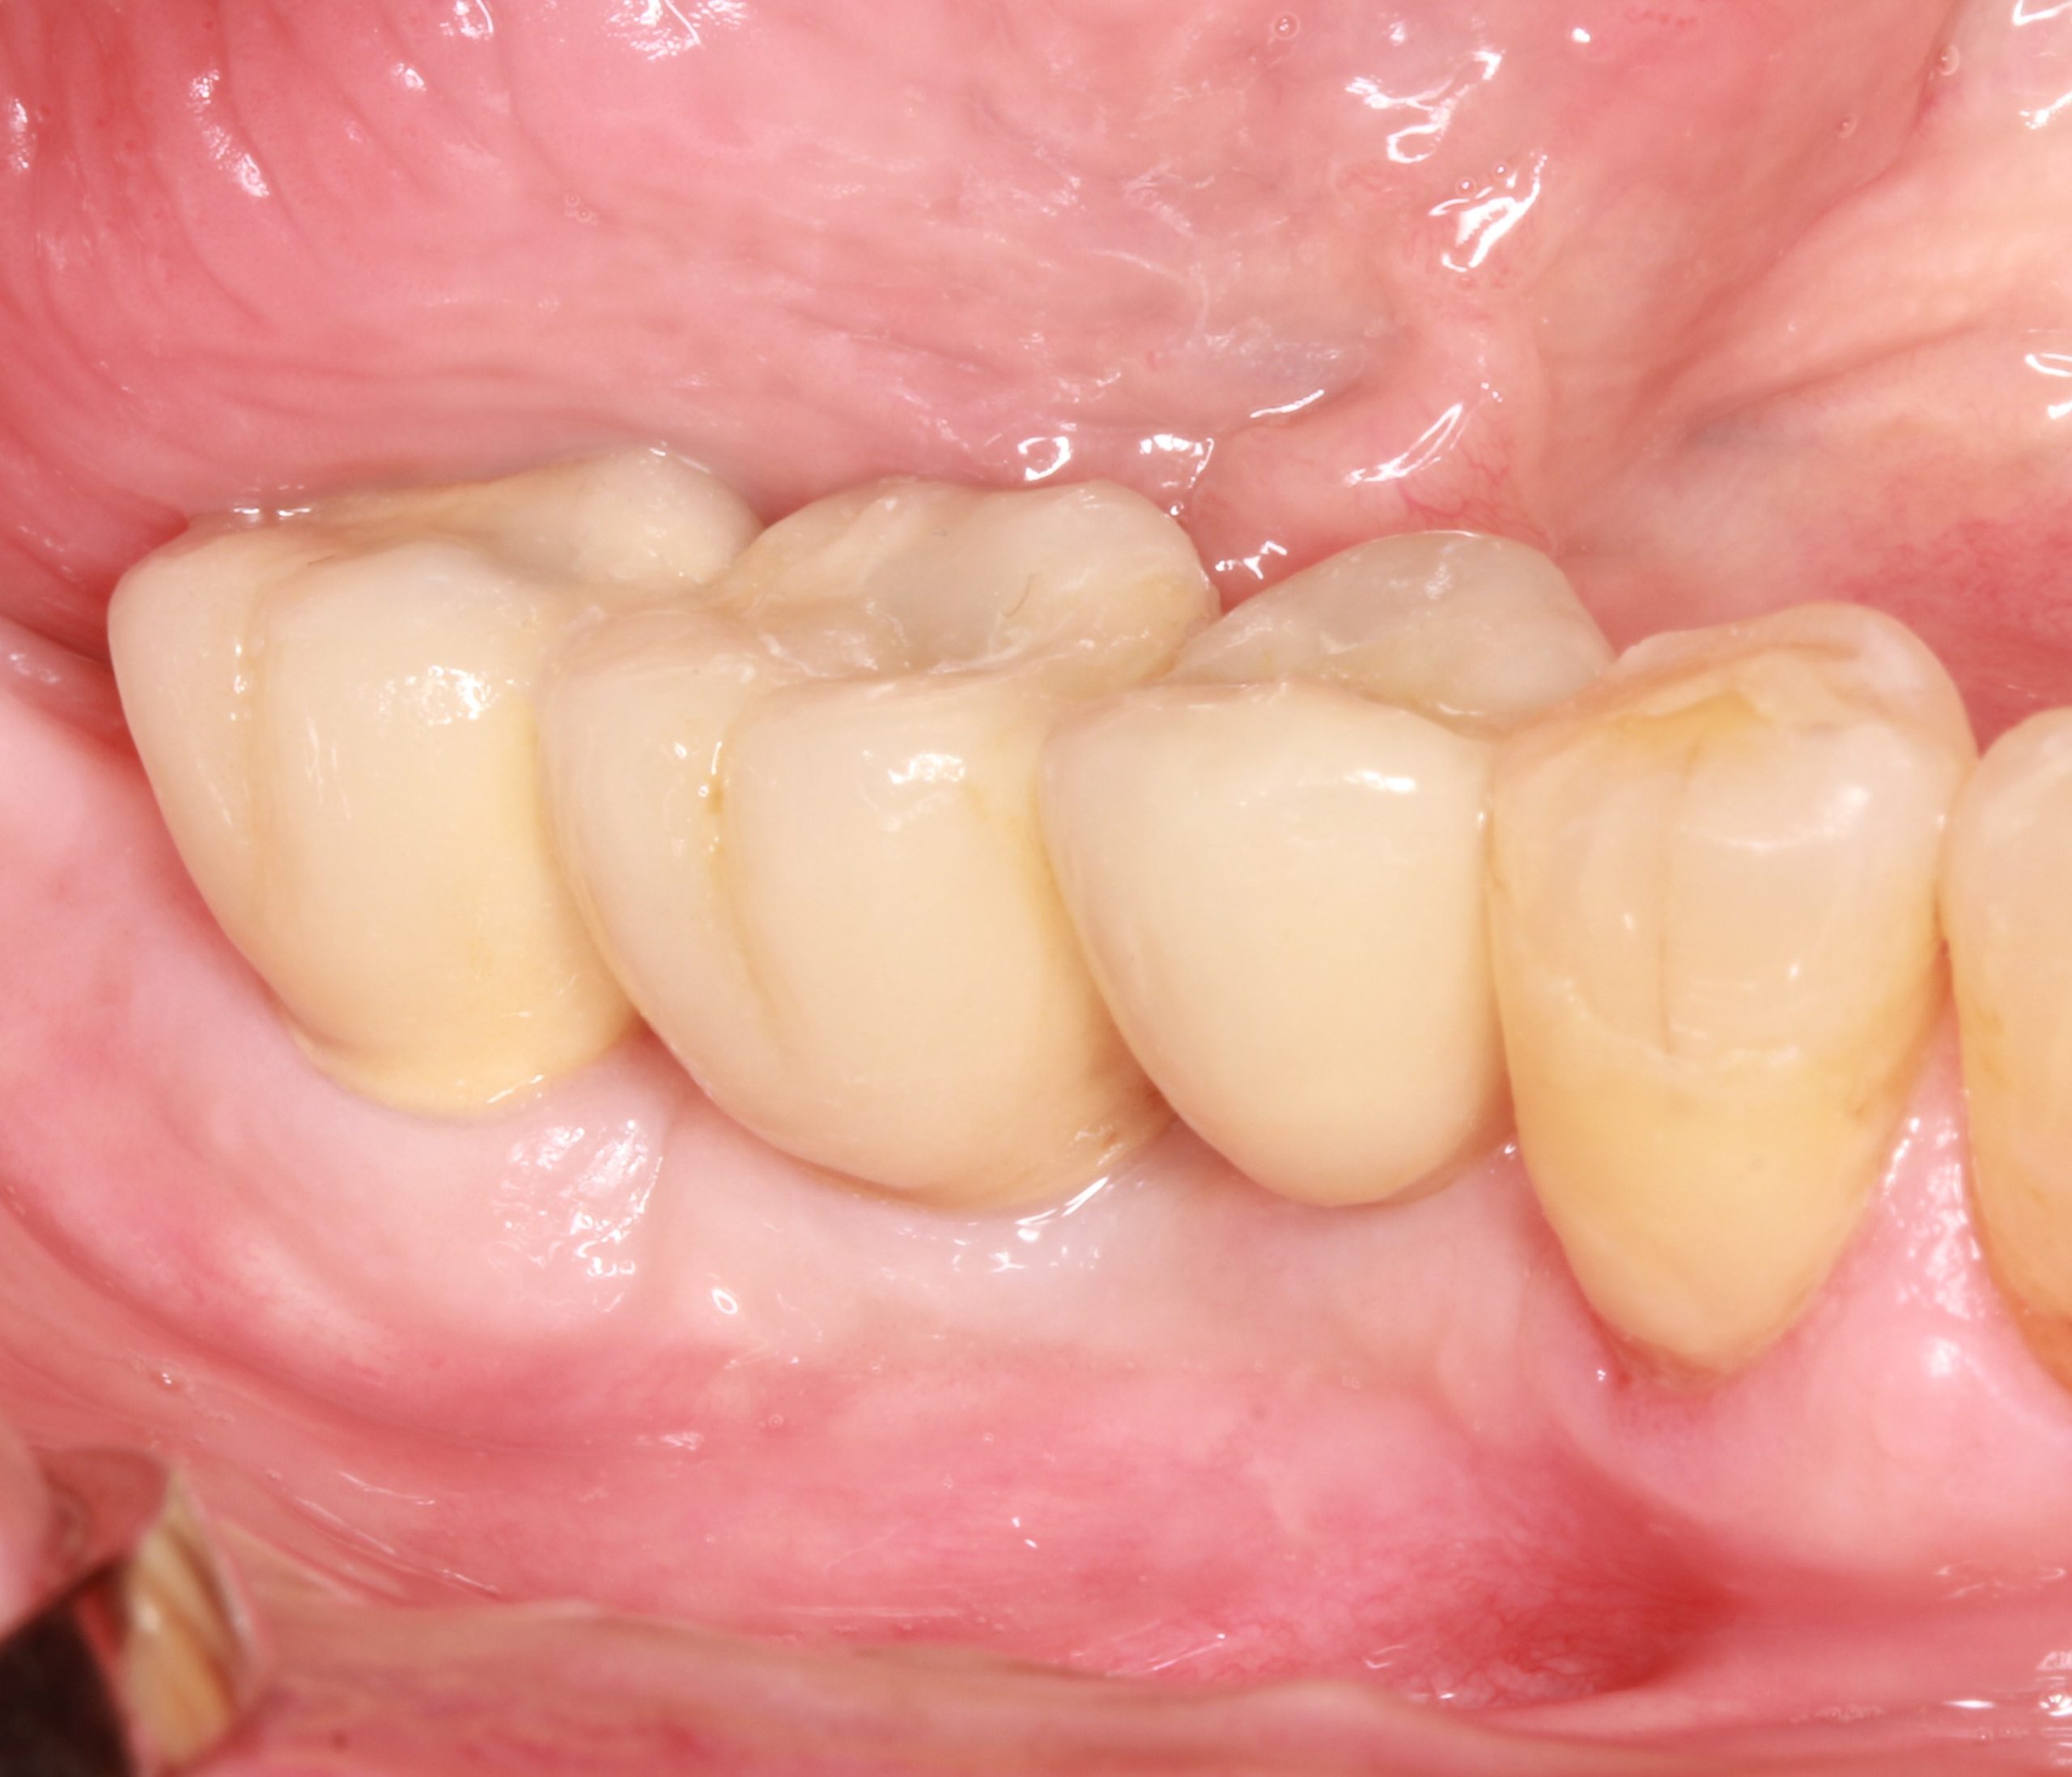

A fixed screw-retained metal-ceramic dental bridge was designed. The trial fitting of the superstructure shows that it fits correctly.

The final prosthesis was screwed into the patient‘s mouth. The patient’s expectations of a functional and esthetic result that is stable and sustainable in the long term were met.